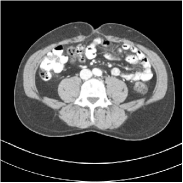

Fig. 2 shows a test example reconstructed using various methods.

Refer to caption

Figure 2: Reconstructions of slice 100 from patient L192 using various methods. The display window is [800 1200] HU.

We observe that PWLS-EP reduces the severe noise and streak artifacts observed in the low-dose FBP images, and the transform learning-based method PWLS-ULTRA further suppresses noise and reconstructs more details of the image such as the zoom-in areas. However, both methods have some blurry artifacts. The standalone FBPConvNet method heavily removes noise and streak artifacts, while introducing several artificial features (e.g., feature indicated by the arrow in the top-right box in Fig. 2). WavResNet denoises the image without introducing artifical features, but still retains some streaks around image boundaries and blurs some details (e.g., feature indicated by the arrow in the bottom-left box in Fig. 2). The state-of-the-art MAP-NN method performs slightly better than WavResNet in terms of suppressing streak artifacts, while it still loses some details as indicated in the zoomed regions. The competing plug-and-play unrolled method—ADMM-Net with WavResNet denoiser—outperforms the standalone WavResNet method, but still has some streak artifacts and blurred details. Compared to these methods, the proposed SUPER methods (SUPER-WRN-EP, SUPER-WRN-ULTRA, SUPER-FCN-EP, and SUPER-FCN-ULTRA) improve the reconstruction quality in terms of removing noise and artifacts, and recovering details more precisely. Two other example comparisons are included in the supplement (Fig. 10 and Fig. 11).